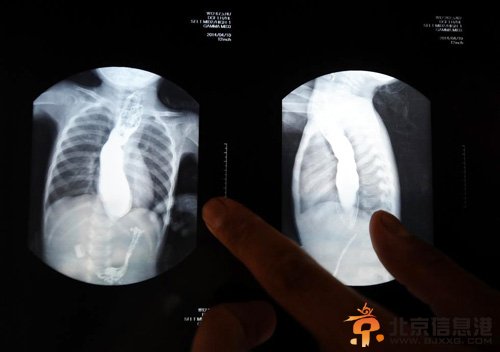

5月22日,王志华在展示女儿一个月前拍的胸片,上面能清晰看到孩子的食管被撑得很大,食物却无法进入胃部。由于王可然不停地呕吐,这样的喂食动作每天要重复无数次。500多天来,天天如此。王志华说,只要女儿能多吃一口,他再苦再累也心甘。